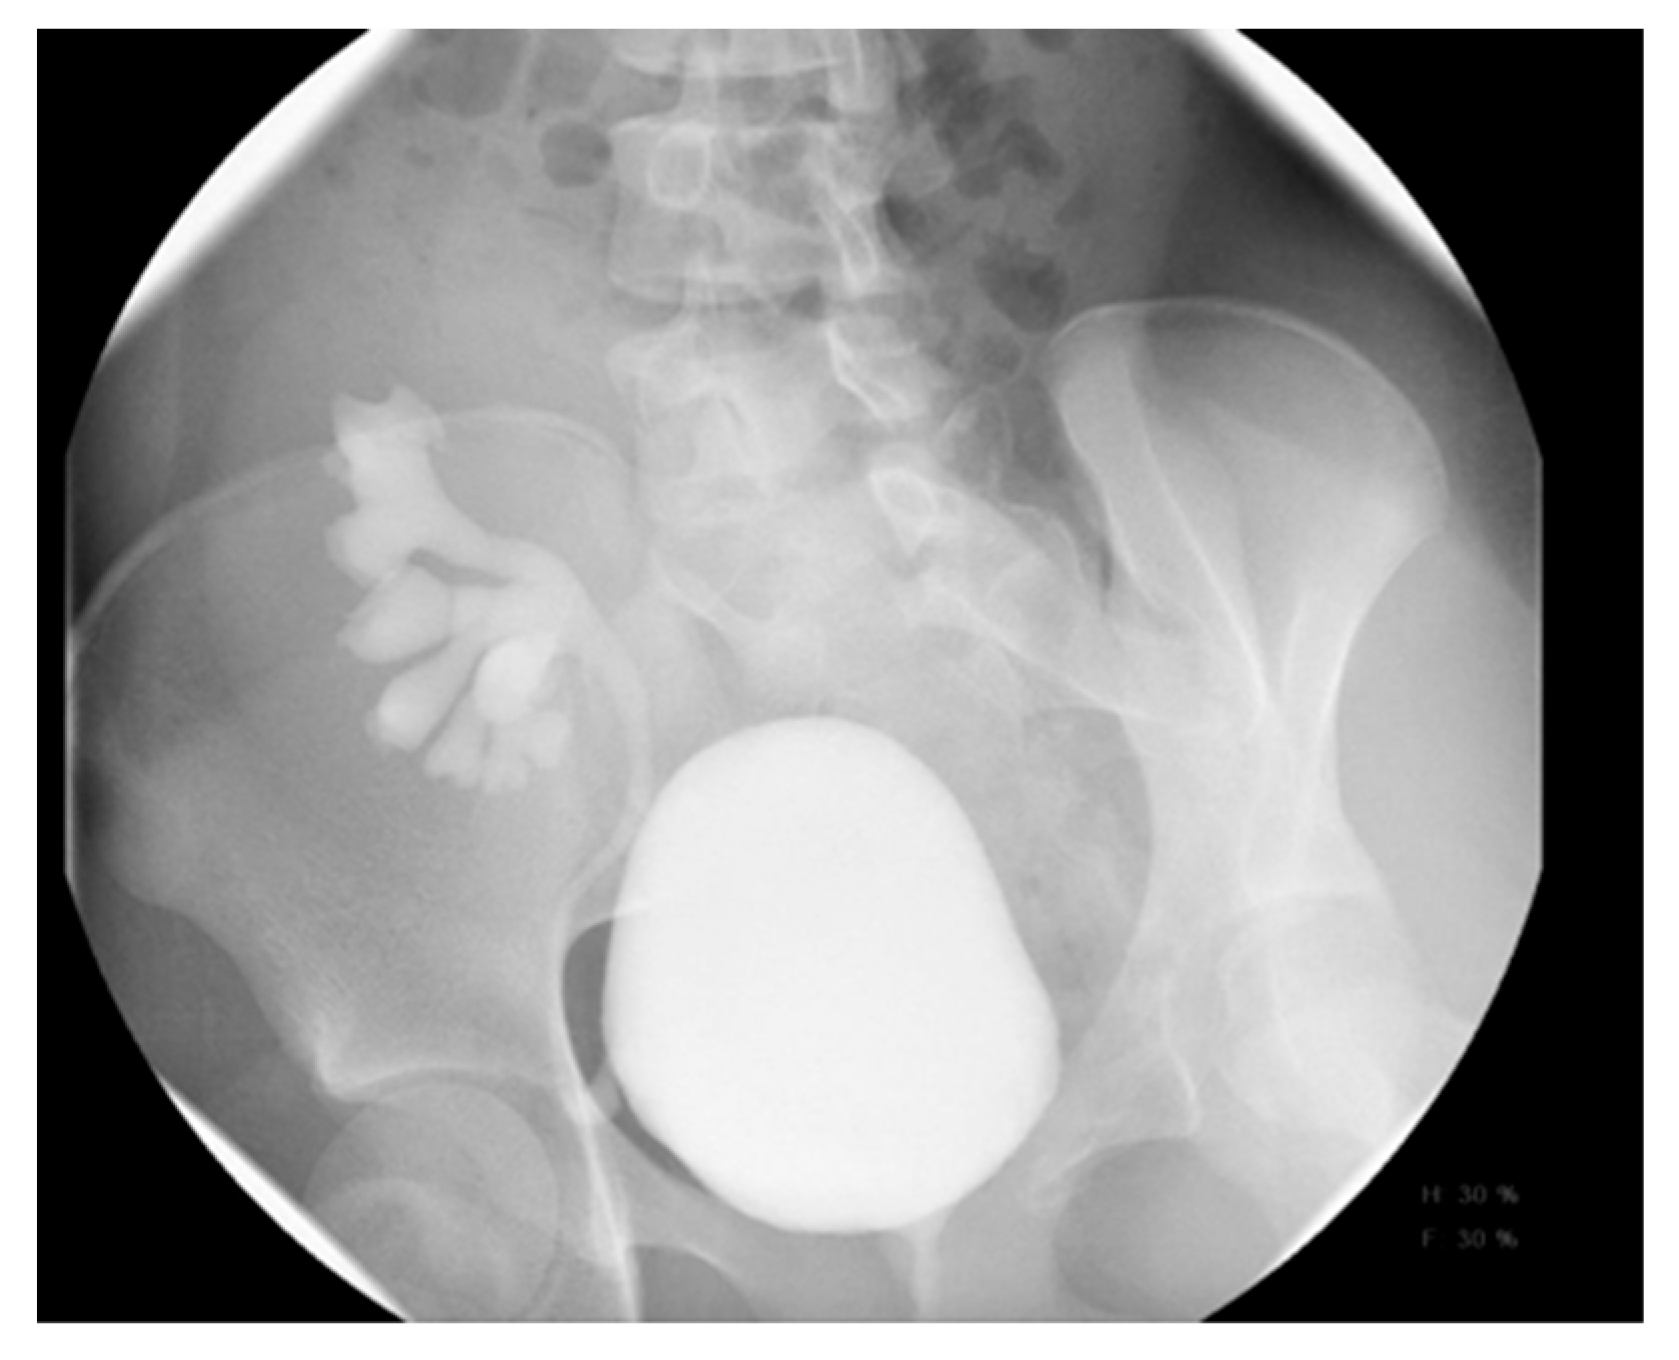

Voiding cystourethrography (VCUG) is the gold standard for detecting vesicoureteral reflux (VUR) and provides valuable information about the bladder and urethra [14]. It is commonly indicated for recurrent urinary tract infections and is often found in cases of hydronephrosis and hydroureter.

An initial abdominal radiograph is taken before filling the bladder to check for calculi or bony abnormalities. The stool burden may also be assessed. Next, the bladder is sterilely catheterized with a feeding tube, and a urine specimen is typically obtained for urinalysis and culture. A contrast material is instilled into the bladder under gravity, and an early filling film is taken to identify any filling defects, such as ureteroceles or bladder tumors. Images are captured before and after voiding, and multiple cycles of bladder filling and voiding can enhance the sensitivity of VCUG in detecting VUR [4,5].

VCUG is the gold standard for diagnosing and grading VUR, offering a comprehensive assessment of the bladder and urethra. VUR is generally suspected when there is urinary tract dilation (UTD), ureteral dilation, or abnormal ultrasound findings, such as uroepithelial thickening or scarring, especially following a first febrile urinary tract infection (UTI). Other indicators include recurrent UTIs, dysfunctional voiding (e.g., neurogenic bladder dysfunction), or bladder outlet obstruction [2]. The grading of VUR is based on the International Reflux Study in Children [38]. Capturing images during voiding is essential for evaluating the urethra and identifying posterior urethral valve (PUV) in male children. A normal urinary bladder appears as a smooth-walled, globular structure, while the urethral walls are smooth, and the posterior urethra is observed as a nondistended, smooth-walled passage (Figure 4). In specific cases, especially in children with trauma or dysuria, a retrograde urethrogram—dedicated exclusively to imaging the urethra—may be preferred over a VCUG [2].

Figure 4. Voiding cystourethrogram. (a) Normal voiding image of a 2-year-old female. (b) Normal voiding image of a 2-year-old male.

Medicina 61 00696 g004